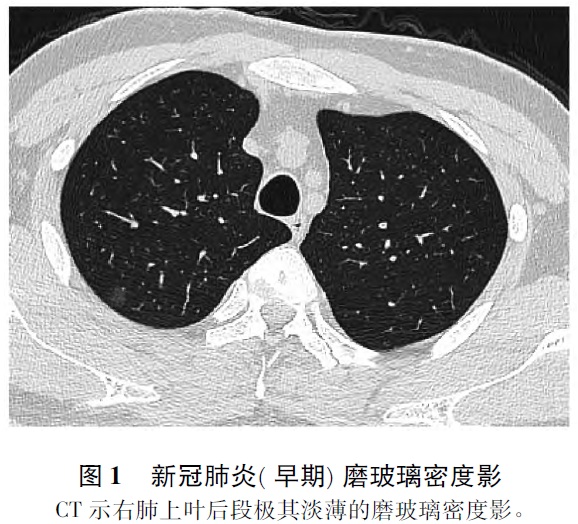

截至2020年2月29日14时,中国累计新型冠状病毒肺炎(以下简称新冠肺炎) 确诊病例79389例,除中国以外全球累计确诊病例4934例,已成为世界关注的严重公共卫生事件。目前,新冠肺炎已纳入《中华人民共和国传染病防治法》规定的乙类传染病,并采取甲类传染病的预防、控制措施。 冠状病毒是一类主要引起呼吸道、肠道疾病的病原体,因病毒颗粒表面有许多规则排列的突起,整个病毒颗粒像帝王的皇冠而得名。2020年2月11日,国际病毒分类委员会宣布将新型冠状病毒命名为严重急性呼吸综合征冠状病毒-2(SARS-CoV-2) ,同日,世界卫生组织(World Health Organization,WHO) 决定将该病毒引起的疾病命名为COVID-19。2020年2月22日,国家卫生健康委员会(以下简称卫健委) 发布《关于修订新型冠状病毒肺炎英文命名事宜的通知》,决定将“新型冠状病毒肺炎”英文名称修订为“COVID-19”,与WHO命名保持一致,中文名称保持不变。 2020年2月29日,《中国-世界卫生组织新型冠状病毒肺炎(COVID-19) 联合考察报告》发布。报告中提出,新冠肺炎病毒是一种动物源性病毒。目前的全基因组基因序列系统进化分析结果显示,蝙蝠似乎是该病毒的宿主,但中间宿主尚未查明。不认为空气传播是主要传播方式,而家庭传播是人际传播主要途径。在传播途径方面,报告称,新冠肺炎在无防护下,通过飞沫和密切接触在感染者和被感染者之间发生传播。尚无新冠肺炎空气传播的报告,且根据现有证据,也不认为空气传播是主要传播方式。但在医疗机构中或可存在因医疗操作产生气溶胶而发生空气传播的可能。根据现有证据,粪-口传播似乎并不是新冠肺炎传播的主要传播方式,其在新冠肺炎病毒传播中的地位和作用仍待明确。人群普遍缺乏对它的免疫力,几乎人人易感,尽管可能存在易感性增加的危险因素,但还需要进一步研究,明确感染后是否具有免疫力。 COVID-19疫情发生后,国家卫健委制定了《新型冠状病毒感染的肺炎诊疗方案》(试行第五版) ,首次将疑似病例中具有胸部影像学特征者纳入临床诊断病例。推荐COVID-19首选和主要的成像技术是胸部高分辨率计算机断层扫描(high resolution computerized tomography,HRCT) (层厚≤1mm) (证据级别:Ⅱ,推荐强度: 强) 。根据病变范围与类型将CT表现分为早期、进展期、重症期与转归期。X线胸片对检出早期病变的敏感度及特异度较低,容易漏诊,仅适应于基层医院,不推荐使用( 重症患者推荐强度: 弱) 。 1 COVID-19影像分期及表现 1. 1 早期 多见于COVID-19发病1周内。双肺单发或多发病灶,多位于肺外周或胸膜下,以中下肺的背段或外侧段多见。病灶多呈胸膜下小叶性、尖端指向肺门方向的楔形或扇形,也可表现为斑片状或类圆形。依据病程时间节点,病灶密度不均,早期多见淡薄的磨玻璃密度影(ground-glass opacity,GGO) ( 图1) ,亦可见网格状影。随着病变进展磨玻璃密度逐渐增高。在磨玻璃密度影内可见支气管血管束增粗(图2) ,或伴有局部小叶间隔网格状增厚。如果早期CT 影像上仅表现为局部的胸膜下磨玻璃密度影,X 线胸片往往难以显示,容易造成漏诊。